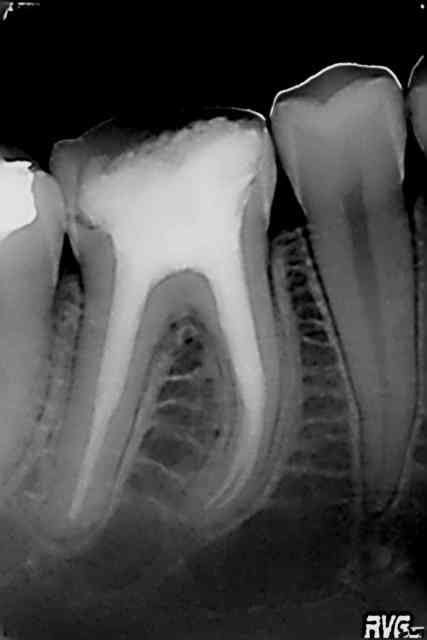

Pour compléter le cas Katia. Je l'ai vue en 2002 pour la première fois (status). N'a pas donné suite aux soins (simples) à l'époque. Revue en urgence en 2003 pour endo de 46.

"Fidélisée" ailleurs et revue en fin 2013 dans l'état que vous connaissez.

Note : elle a l'air mieux sous subutex car elle vient à ses rendez vous. Alors oui ca vaut le coup de faire un petit quelque chose fusse au tarif CMU.

Regarde l'évolution du cas Katia sur 46 :

en 2002 , Chicot29 traite parfaitement cette dent , 10 ans plus tard sur nouveau status elle n'est plus présente , et la situation à continuée de se dégrader .

Reconstitution moignons technique directe 15/25 et provisoires , avulsion des molaires trop atteintes PAP .

T'es pas a l'apex tu vaux rien :p

J'étais nul en endo en 2002.))))